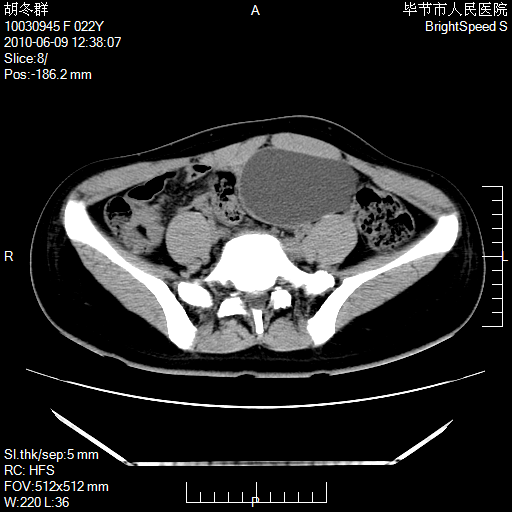

患者23岁,发现腹部包块3月。

左侧卵巢囊腺瘤或囊腺癌

盆腔内囊性占位性病变;考虑左侧卵巢囊腺瘤。

有分隔、壁薄,支持考虑左侧卵巢囊腺瘤。

左侧卵巢浆液性囊腺瘤。

支持考虑左侧卵巢囊腺瘤;宫腔积液。

有分隔、壁薄,支持考虑左侧卵巢囊腺瘤。排尿后,膀胱缩小,由于重力作用,肿块下移就到了膀胱位置,很好理解。